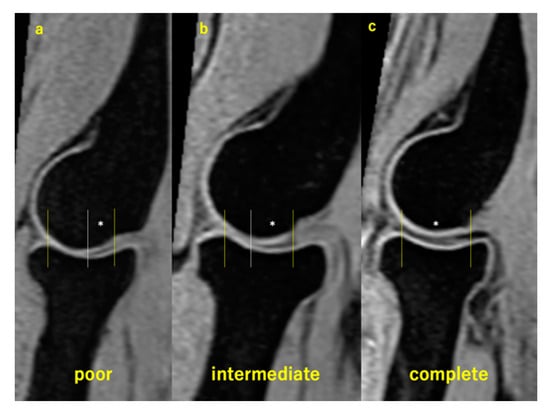

2.7. Evaluation of Pain and Discomfort